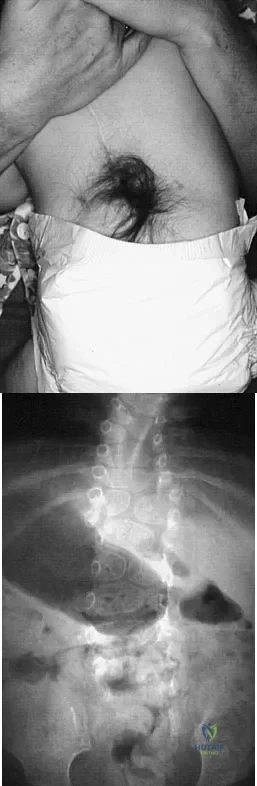

A 58-year-old woman is seen in the emergency department after falling at home. History reveals that she underwent right total knee arthroplasty 2 years ago. Radiographs are shown in Figures 56a and 56b. What is the most appropriate treatment?

The radiographs show an oblique periprosthetic distal femoral fracture. Of the options listed, open reduction and internal fixation is the most appropriate surgical option because a well-fixed, posterior stabilized closed box femoral component is present. Nonsurgical methods are not favored because of the highly displaced, unstable fracture pattern and prolonged immobility. Revision with a stemmed component is an option but would sacrifice more bone stock in this younger patient. Moran MC, Brick GW, Sledge CB, et al: Supracondylar femoral fracture following total knee arthroplasty. Clin Orthop 1996;324:196-209. Raab GE, Davis CM III: Early healing with locked condylar plating of periprosthetic fractures around the knee. J Arthroplasty 2005;20:984-989.